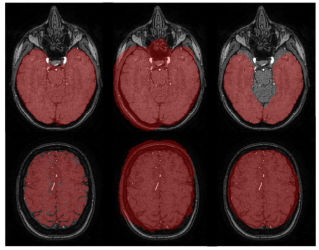

QU-BraTS: MICCAI BraTS 2020 Challenge on Quantifying Uncertainty in Brain Tumor Segmentation–Analysis of Ranking Metrics and Benchmarking Results

Raghav Mehta, Angelos Filos, Ujjwal Baid, Chiharu Sako, Richard McKinley, Michael Rebsamen, Katrin Dätwyler, Raphael Meier, Piotr Radojewski, Gowtham Krishnan Murugesan, Sahil Nalawade, Chandan Ganesh, Ben Wagner, Fang F Yu, Baowei Fei, Ananth J Madhuranthakam, Joseph A Maldjian, Laura Daza, Catalina Gómez, Pablo Arbeláez, Chengliang Dai, Shuo Wang, Hadrien Raynaud, Yuanhan Mo, Elsa Angelini, Yike Guo, Wenjia Bai, Subhashis Banerjee, Linmin Pei, Murat AK, Sarahi Rosas-González, Illyess Zemmoura, Clovis Tauber, Minh H Vu, Tufve Nyholm, Tommy Löfstedt, Laura Mora Ballestar, Veronica Vilaplana, Hugh McHugh, Gonzalo Maso Talou, Alan Wang, Jay Patel, Ken Chang, Katharina Hoebel, Mishka Gidwani, Nishanth Arun, Sharut Gupta, Mehak Aggarwal, Praveer Singh, Elizabeth R Gerstner, Jayashree Kalpathy-Cramer, Nicolas Boutry, Alexis Huard, Lasitha Vidyaratne, Md Monibor Rahman, Khan M Iftekharuddin, Joseph Chazalon, Elodie Puybareau, Guillaume Tochon, Jun Ma, Mariano Cabezas, Xavier Llado, Arnau Oliver, Liliana Valencia, Sergi Valverde, Mehdi Amian, Mohammadreza Soltaninejad, Andriy Myronenko, Ali Hatamizadeh, Xue Feng, Quan Dou, Nicholas Tustison, Craig Meyer, Nisarg A Shah, Sanjay Talbar, Marc-Andr Weber, Abhishek Mahajan, Andras Jakab, Roland Wiest, Hassan M Fathallah-Shaykh, Arash Nazeri, Mikhail Milchenko, Daniel Marcus, Aikaterini Kotrotsou, Rivka Colen, John Freymann, Justin Kirby, Christos Davatzikos, Bjoern Menze, Spyridon Bakas, Yarin Gal, Tal Arbel

arXiv